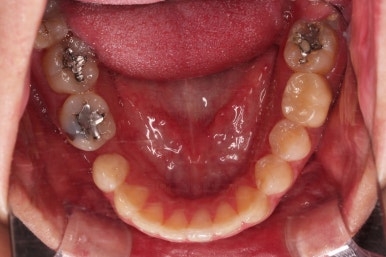

임플란트 완료시 모습인데요.

임플란트 식립부터 완료까지 시간이 걸리다보니 최종 종료까지는 총 19개월이 걸렸습니다.

교합도 잘 맞고 임플란트도 잘 완성되었네요.

매복치아도 손상 없이 잘 배열이 되었고, 교합도 좋게 마무리 되었습니다.